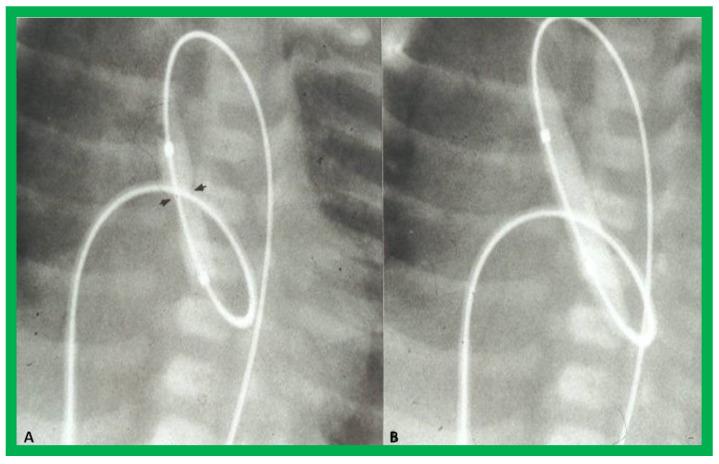

While investigating the outcomes of balloon dilatation procedures in patients with congenital obstructive lesions of the heart, several parallel observations were made. The purpose of this review is to present these observations/phenomena/innovations related to balloon dilatation of pulmonary stenosis (PS), aortic stenosis (AS), and aortic coarctation (AC). In subjects who had balloon pulmonary valvuloplasty (BPV), development of infundibular obstruction, electrocardiographic (ECG) changes, changes in right ventricular filling, role of balloon/annulus ratios on the results of BPV, and double balloon vs. single balloon BPV will be reviewed. In patients who had balloon aortic valvuloplasty (BAV), causes of aortic insufficiency and trans-umbilical venous approach for BAV are tackled. In children who had balloon angioplasty (BA) of AC, aortic remodeling and biophysical response after BA of AC are discussed.

在研究患有先天性心脏阻塞性病变患者的球囊扩张手术结果时,进行了几项平行观察。本综述的目的是介绍这些与肺动脉狭窄(PS)、主动脉狭窄(AS)和主动脉缩窄(AC)球囊扩张相关的观察结果/现象/创新。在接受球囊肺动脉瓣成形术(BPV)的受试者中,将对漏斗部梗阻的发展、心电图(ECG)变化、右心室充盈变化、球囊/瓣环比率对BPV结果的作用以及双球囊与单球囊BPV进行综述。在接受球囊主动脉瓣成形术(BAV)的患者中,探讨主动脉瓣关闭不全的原因以及BAV的经脐静脉途径。在接受AC球囊血管成形术(BA)的儿童中,讨论AC球囊血管成形术后的主动脉重塑和生物物理反应。